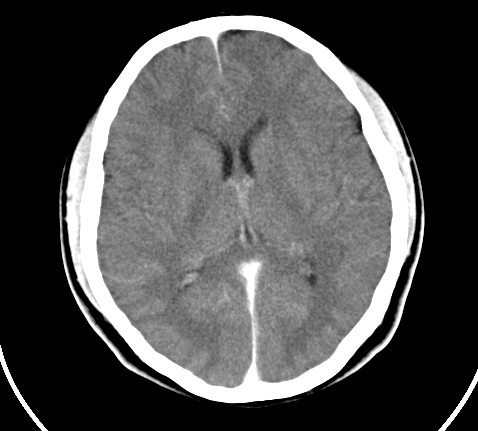

胸部